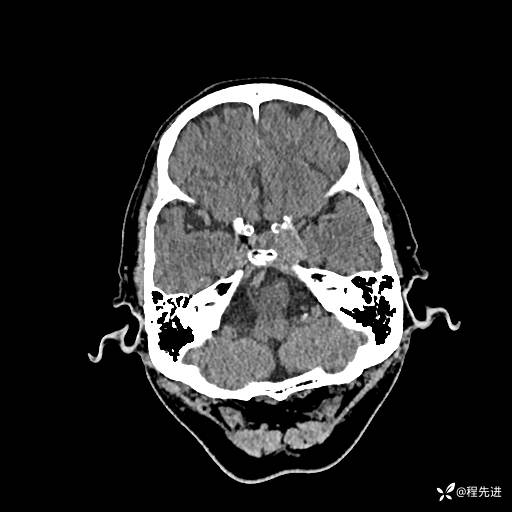

患者性别:男

患者年龄:74岁

简要病史:出现视物重影2月余,未予重视,2月来症状逐渐加重

实验室检查:无特殊

CT平扫: